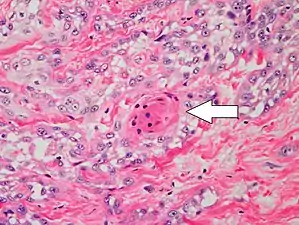

Two types of multinucleated cells may be seen: the first will present as a multinucleated giant cell, and the second will appear as a dyskeratotic cell engulfed in the cytoplasm of a keratinocyte. Occasionally, cells of the upper epidermis will undergo vacuolization, demonstrating an abundant and strongly eosinophilic cytoplasm. There may be a mild to moderate lymphohistiocytic infiltrate detected in the upper dermis.[12]

Histopathology of squamous-cell carcinoma in situ (black arrow), compared to normal skin, showing marked atypia.

Squamous-cell carcinoma in situ, showing prominent dyskeratosis and aberrant mitoses at all levels of the epidermis, along with marked parakeratosis.[12]